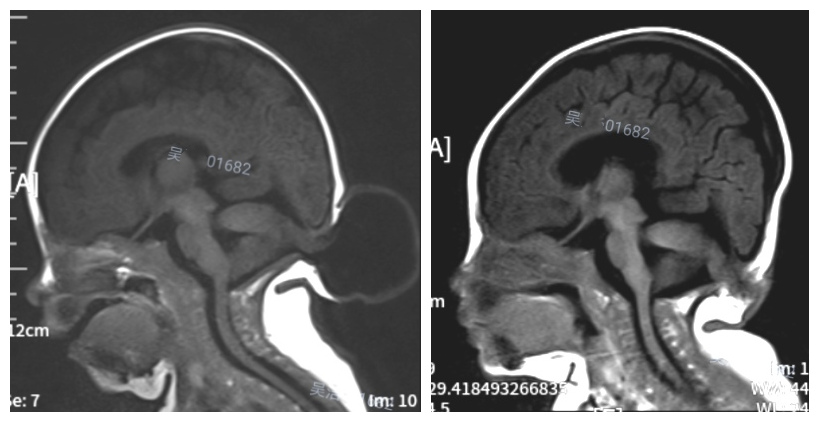

近日,兰大二院小儿神经外科专业组收治了一名出生25天的患儿,该患儿生后即发现脑后有个核桃大的包块。随着孩子一天天长大,包块也跟着疯长,不到一个月,包块体积就增大了两倍多。通过检查,发现该女婴患上的是一种常见的神经系统先天性畸形——脑膜脑膨出。孩子后脑的包块不是肿瘤,确切地说应该是一包‘水’,一包由病变的脑组织、脑膜和脑脊液积聚形成的‘水’。这包“水”形成的主要原因,是女婴先天性后枕部颅骨缺损,在孩子生长的过程中,她的部分小脑和脑膜及脑脊液通过颅骨缺损处汇集到包块里,形成现在的样子。这种疾病发展到后期可引起一系列并发症,如果包膜皮肤破溃,感染,甚至蛛网膜下腔和颅内感染,后果极其严重。

这种病例通常可以通过手术,先抽出积水,然后切除膨出脑膜,再进行修补手术。“这个手术面临三个困难:第一,患者年纪小,手术输液时难以找到血管;第二,患者气管只有成人小拇指粗细,麻醉后插管困难;第三,手术中出血量大,患者体内血液少,可能引起失血过多造成死亡。”3月17日,在神经外科李强主任的指导下,我院多个科室协同配合,由贺振华副主任医师主刀奋战3个小时,从包块中抽出300ml的脑积水,并且成功切除了包块,孩子终于能够平躺着睡觉了。